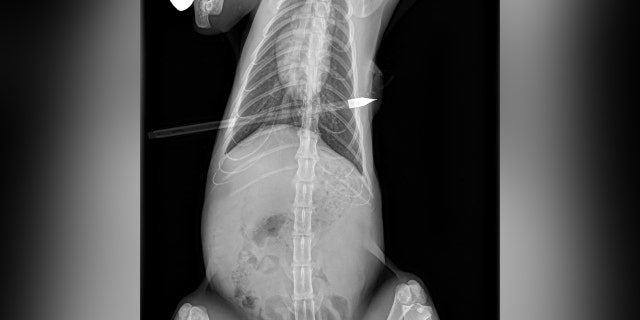

Shelter officials quickly got Santana to Affiliated Veterinary Service, where he was given lifesaving surgery to remove the arrow, which pierced both of his lungs, causing them to collapse.

A Dearborn, Michigan, cat was shot with an arrow and underwent lifesaving surgery. (Photo from Friends for Animals of Metro Detroit Facebook)

Santana the cat underwent lifesaving surgery to have an arrow removed from his body, which caused both lungs to collapse. (Photo from Friends for Animals of Metro Detroit Facebook)